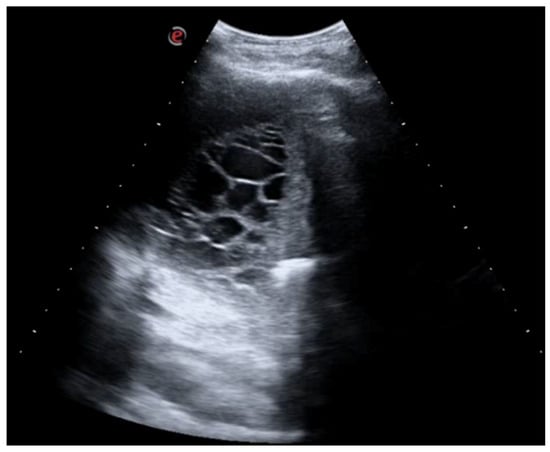

A 26-year-old man was admitted to our hospital for worsening dyspnea at rest and pain in the right hemithorax. The patient complained of a fever (39.5 °C) and productive cough for about 1 week, with mild hemoptysis in the days prior. His medical history included bilateral bronchiectasis and bronchial asthma, for which he received inhalation therapy with a long-acting antimuscarinic agent, long-acting bronchodilator, and inhaled corticosteroid. He had no family history of respiratory disease and had been tested for cystic fibrosis transmembrane regulator (CFTR) gene mutations, with negative results. The patient did not smoke cigarettes, drink alcohol, or use recreational drugs. An arterial blood gas (ABG) analysis showed acute hypoxemic normocapnic respiratory failure; therefore, oxygen therapy with a 28% FiO2 via a Venturi mask was administered. Chest radiography showed an area of opacification at the right base. Empiric antibiotic therapy with 12 mg/kg teicoplanine (Q8H) and 4.5 g piperacillin/tazobactam (Q6H) was then started on suspicion of community-acquired pneumonia. Blood tests upon his admission showed leukocytosis (WBC 18.84 × 109 cells/L) with predominant neutrophils (14.5 × 109 cells/L). Legionella and pneumococcal antigens in his urine were negative. Blood cultures after 72 h were negative. Chest ultrasonography revealed a multiloculated effusion (Figure 1).

Figure 1. Chest US at admission. Multiloculated pleural effusion.